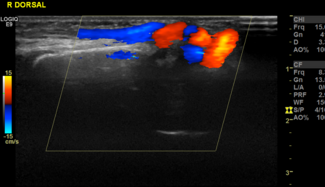

This is a unique case of a 15-month-old female infant who presented with a pulsatile mass on the right wrist. An arteriogram showed a communication between the radial artery and cephalic vein.